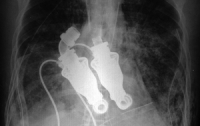

Ученые создали «тайное» искусственное сердце

У нового трансплантата нет пульсирующих сокращений - сердцебиения